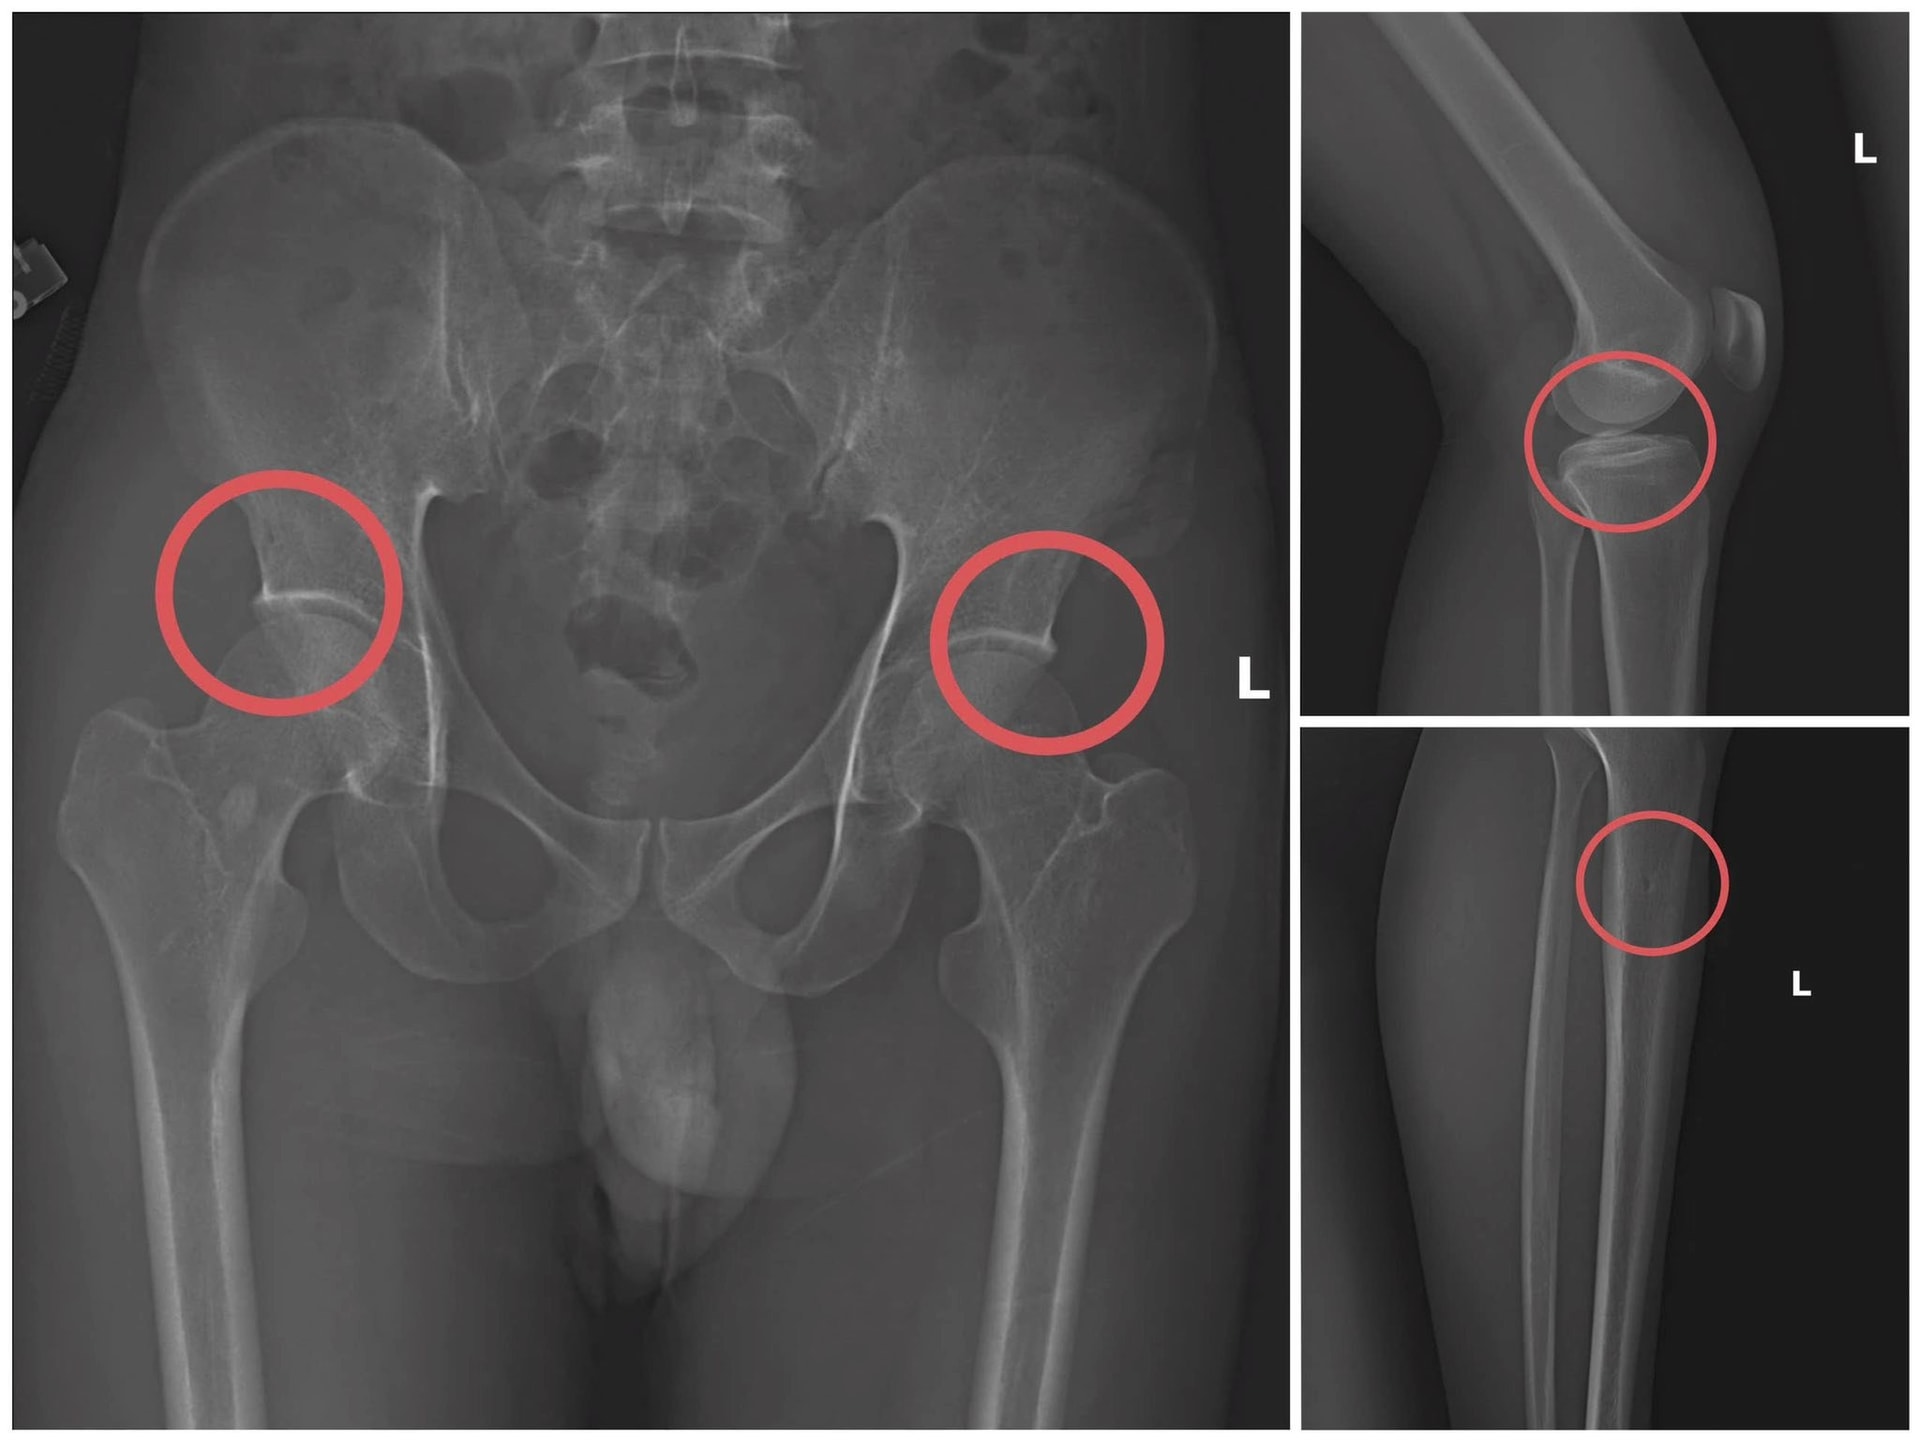

Châu bị xác định đã sử dụng thuốc gây mê, sau đó dùng vật cứng tác động vào xương người mua bảo hiểm để tạo ra các vết nứt, vỡ xương giống tai nạn thật. Sau khi gây thương tích, Châu hướng dẫn dựng hiện trường giả như ngã điện, trượt chân… để hoàn thiện hồ sơ yêu cầu chi trả.

Theo đánh giá của lãnh đạo Công an tỉnh Phú Thọ, thủ đoạn này đặc biệt tàn nhẫn, coi thường sức khỏe, tính mạng người tham gia, đồng thời có tính toán nhằm tạo thương tích tại những vị trí có mức chi trả cao, gây khó khăn cho việc phát hiện gian lận.